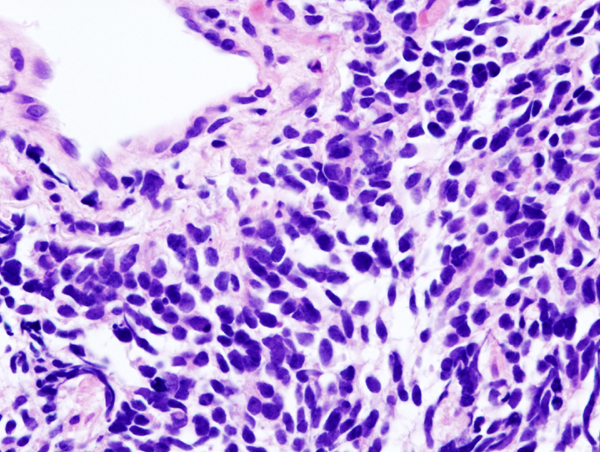

Lung small cell carcinoa by core needle biopsy, Wikimedia Commons

• 조직학적 특징

- 작은 크기의 세포

- salt-and-pepper chromatin, nuclear molding

- scant cytoplasm

- 광범위한 괴사

- electron microscopy 상 dense-core neurosecretory granules 관찰 가능

면역화학염색: chromogranin, synaptophysin, CD56 (+)